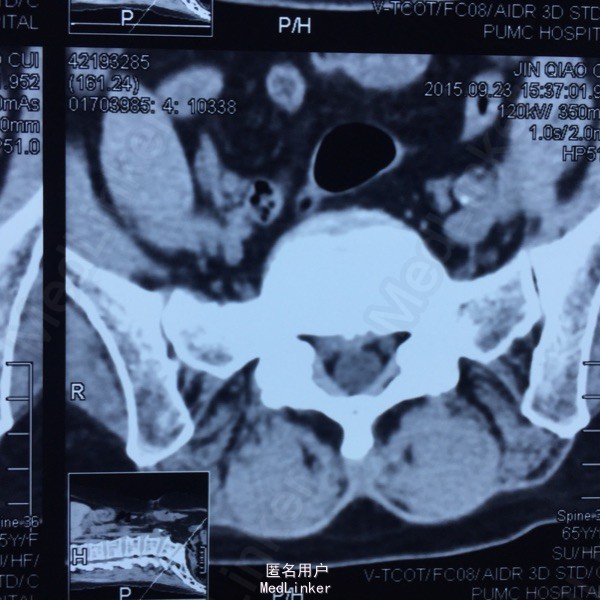

L5-S1左侧棘旁压痛(+),右小腿外侧针刺觉稍弱,右侧跟腱反射稍弱。 腰椎CT提示L5-S1间盘突出,偏右侧。 腰椎X线片提示髂嵴偏高,L5横突肥大。

L5-S1椎间盘突出 C5-6 ACDF术后 拟行椎间孔镜手术

因为穿刺通道比较狭小,进入椎间盘时偏杨氏,采用由内而外的方式减压神经根,用镜下弹性弯钳较好完成了神经根减压。